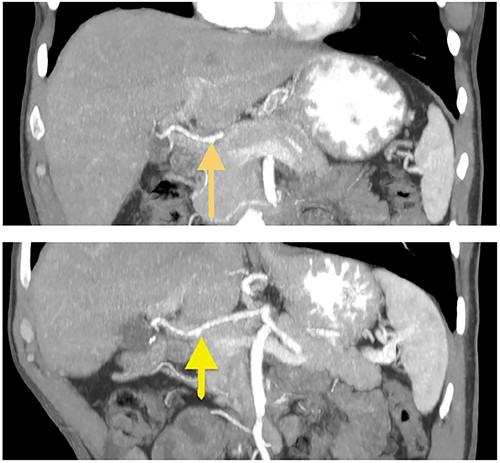

A 57-year-old white male reached for medical advice after 15 months of progressive dysphagia and weight loss. The patient had a history of ‘kissing’ duodenal ulcers (DU) which caused perforation with concomitant posterior DU bleeding 10 years ago; at the time he underwent exploratory laparotomy and gastroduodenal artery (GDA) ligation as well as ‘Graham patch’ procedure for the perforated DU. A few months later the patient developed pyloric stenosis and gastric outlet obstruction, for which he was treated with re-exploration and gastrojejunal anastomosis-bypass (Fig. 1). Clinical symptoms of dysphagia, regurgitation and reflux led to esophagogastroduodenoscopy 2 months prior to admission, which revealed esophageal lumen stenosis, Barrett’s esophagus and a sizeable mixed type hiatus hernia. Endoscopically acquired biopsy confirmed high-grade dysplasia on the background of Barrett’s esophagus, progressing to invasive esophageal adenocarcinoma. His past medical history was significant for a 4.4 cm infrarenal abdominal aorta aneurysm and hypertension. The patient was admitted to the hospital for nutritional support and further preoperative evaluation. Contrast-enhanced computed tomography (CT) angiography performed to evaluate vasculature of the stomach revealed absence of the RGEA as expected since GDA was ligated in his previous operation (Fig. 2).After complete staging and multidisciplinary meeting discussion the decision was to proceed with primary surgery. Histopathology exam revealed a gastroesophageal adenocarcinoma staged as pT3N1 [3].

Coronal CT images of stomach’s vascular supply (arrows showing RGEA absence).